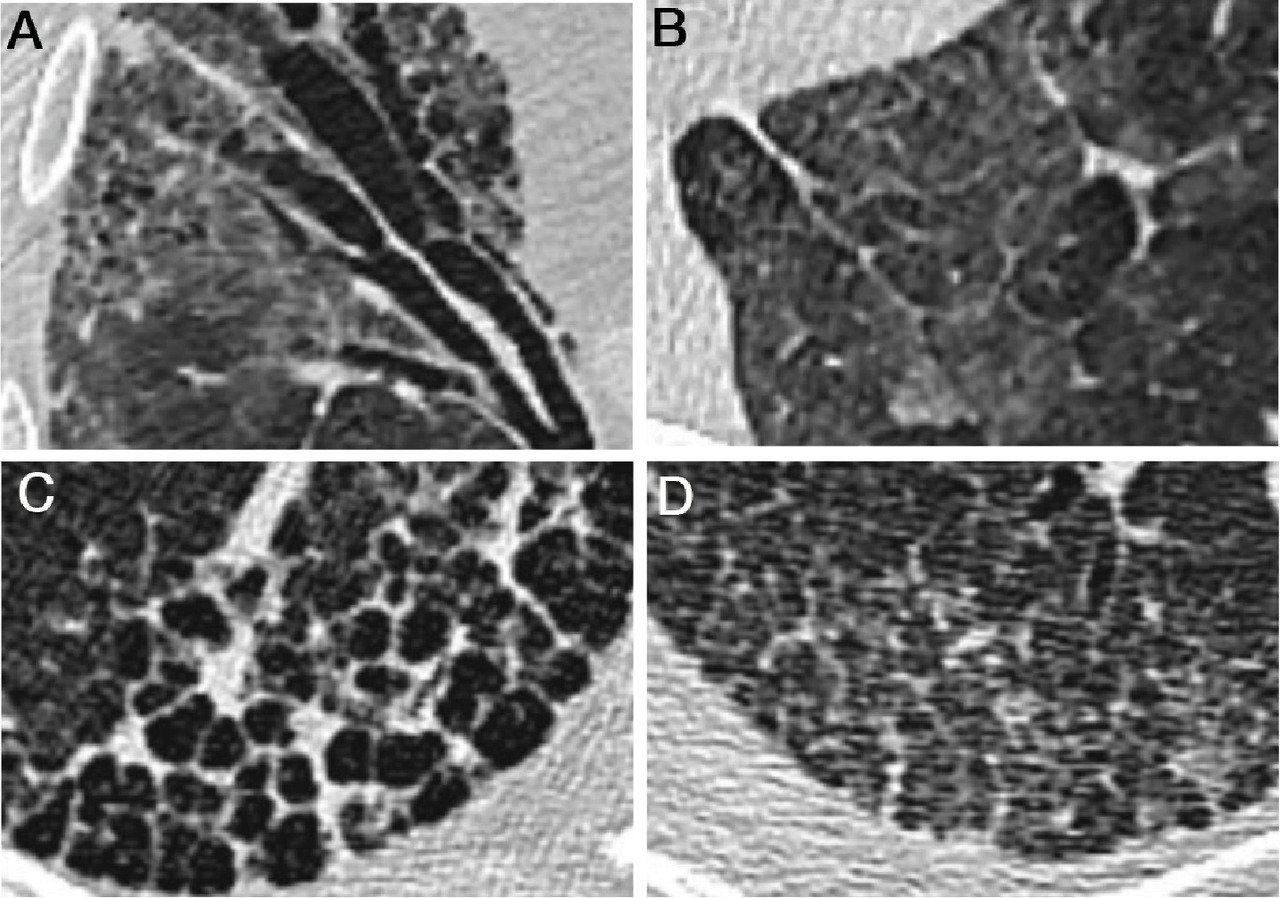

Bronchectasies : dilatations localisées ou diffuses des bronches. Celles de traction peuvent être causées par la fibrose et se manifester par des espaces aériques tubulaires déformés, avec un diamètre bronchique plus grand que celui de l’artère pulmonaire associée (figure A).

Opacité en verre dépoli : opacité modérée qui n’efface pas les contours des vaisseaux pulmonaires et des parois bronchiques, contrairement à la condensation. Étendue et hétérogène, elle peut prendre un aspect en mosaïque et être due à une pathologie vasculaire ou bronchiolaire. Visible aussi dans les pathologies interstitielles (figure B). Un nodule en verre dépoli fait évoquer un cancer bronchopulmonaire à composante lépidique (non invasif, avec respect de l’architecture pulmonaire).

Rayon de miel : stade final et irréversible de la destruction pulmonaire par la fibrose. Kystes jointifs de petite taille, le plus souvent inférieurs au centimètre et limités par une paroi d’épaisseur variable (figure C).

Réticulations intralobulaires : petites lignes entrecroisées formant une réticulation millimétrique, volontiers superposée à du verre dépoli (figure D). Elles sont généralement visibles dans les pneumopathies interstitielles fibrosantes.